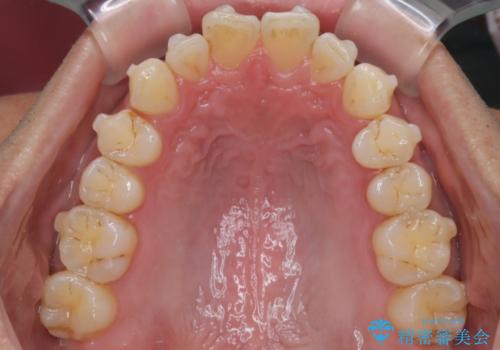

【インザライン】前歯の凸凹を治したい

- 前歯の凸凹を主訴に来院されました。

下顎位が右方に変異しており、外科矯正も提案しましたが患者様は希望されず、インビザラインにて治療を完了しております。

叢生のスペースを確保するために、臼歯部の遠心移動を行っています。

今回の治療計画は上顎の正中を顔と揃えることを優先しています。